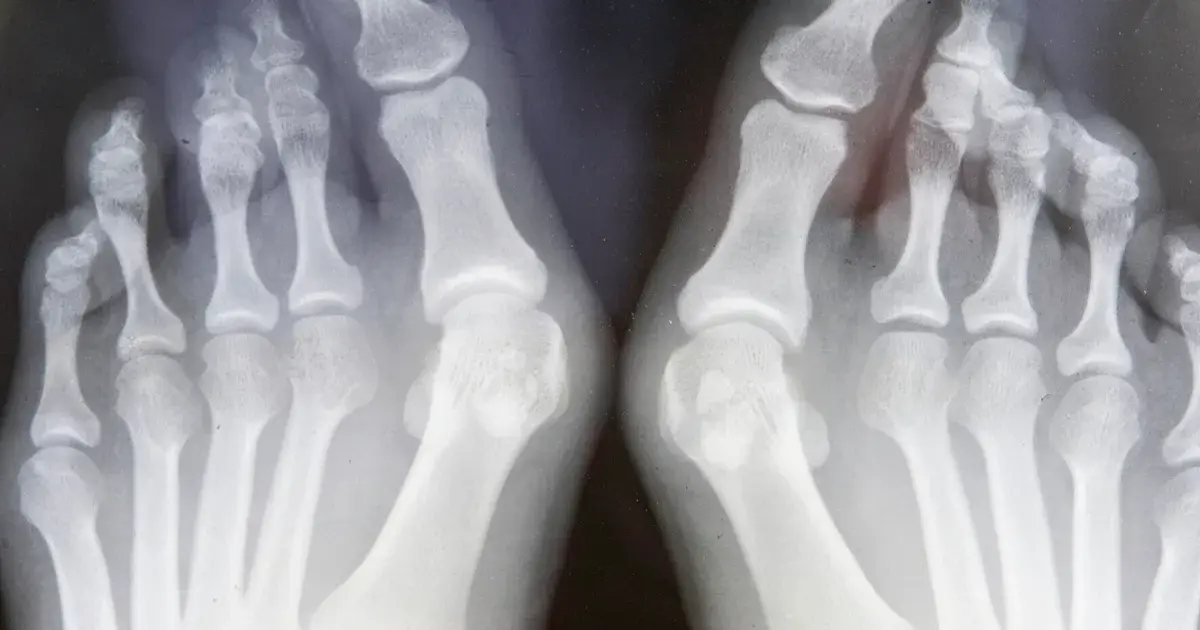

پزشکان شدت هالوکس والگوس را بر اساس زوایای اندازه گیری شده در عکس های رادیوگرافی دسته بندی میکنند. اگرچه دانستن جزئیات این زوایا برای یک تولیدکننده ضروری نیست، اما درک دسته بندی کلی آن به طراحی هدفمندتر کمک میکند:

- خفیف: انحراف جزئی وجود دارد و برآمدگی کوچک است. درد معمولا فقط پس از پوشیدن کفش های تنگ برای مدت طولانی رخ میدهد. در این مرحله، کفش هایی با پنجه پهن و رویه انعطاف پذیر میتوانند بسیار موثر باشند.

- متوسط: انحراف قابل مشاهده است و بونیون برجسته تر شده است. ممکن است انگشت شست به زیر انگشت دوم حرکت کند. درد متناوب بوده و ممکن است فعالیت های روزمره را مختل کند. طراحی کفش در این مرحله باید علاوه بر فضای کافی، شامل پشتیبانی از قوس کف پا برای کنترل پرونیشن نیز باشد.

- شدید: انحراف بسیار زیاد است و شست پا به شدت روی انگشتان دیگر همپوشانی دارد. درد میتواند مزمن و ناتوان کننده باشد و مفصل دچار آرتروز و خشکی شده است. در این مرحله، کفش ها باید قابلیت جا دادن ارتزهای سفارشی را داشته باشند و ممکن است نیاز به طراحی های کاملا سفارشی باشد.